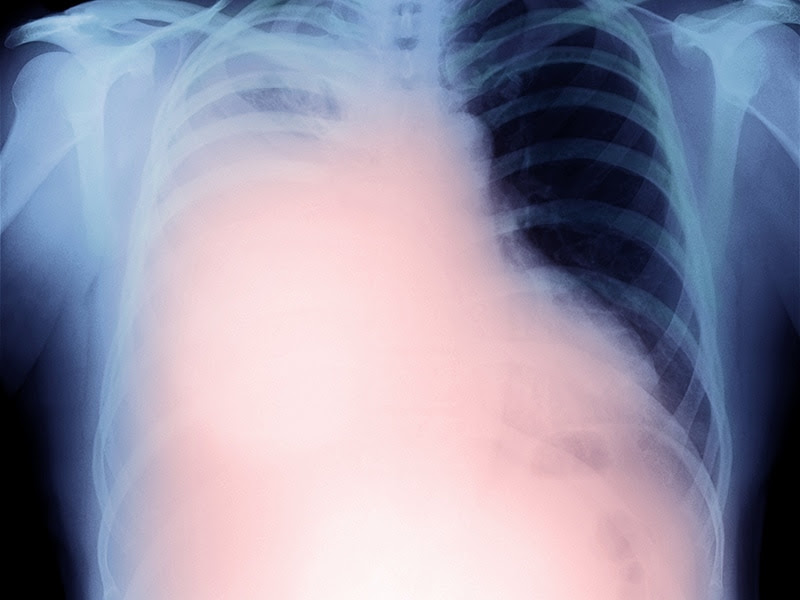

Mesotelioma pleural

Mesotelioma pleural from hdstatic.net